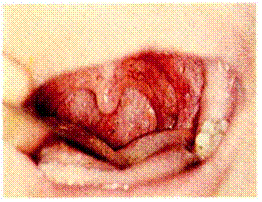

230. Острый флегмонозный ларин- 231. Флегмонозно-абсцедирующий гит. Отек черпаловидных хрящей ларингит. В задних отделах верхне-и черпалонадгортанных складок. го этажа гортани определяется